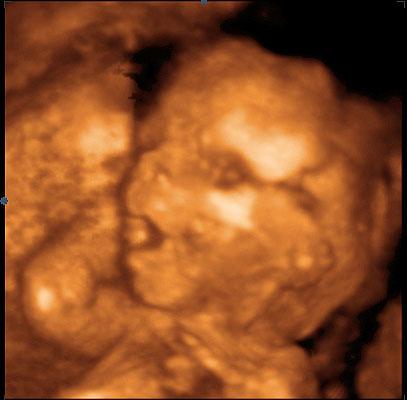

Kolem 20. týdne těhotenství byste měla absolvovat II. ultrazvukový screening (20–22. týden těhotenství). Toto vyšetření se specializuje na odhalení případných vývojových vad plodu, dále se zjišťuje uložení placenty, množství plodové vody a růst plodu. V případě nejasného nálezu nebo zvýšeného rizika se doplňuje podrobné vyšetření srdce plodu lékařem – specialistou.

Na vyšetření ultrazvukem vám rádi vytisknou obrázek vašeho miminka!

Opět se přichystejte na vyšetření v prenatální poradně. Podstoupíte ultrazvukový screening plodu (lze v intervalu 18. až 20. týden). Jeho cílem je zhodnotit růst plodu a stav jednotlivých orgánových skupin. Pokud by plod měl nějakou strukturální odchylku (srdeční vada, obličejový rozštěp), lze ji odhalit.

Sonogram plodu ve 20. týdnu těhotenství: zavřená očička (víčka jsou dosud srostlá) a pootevřená pusinka navozují dojem, že je plod ospalý a zívá.